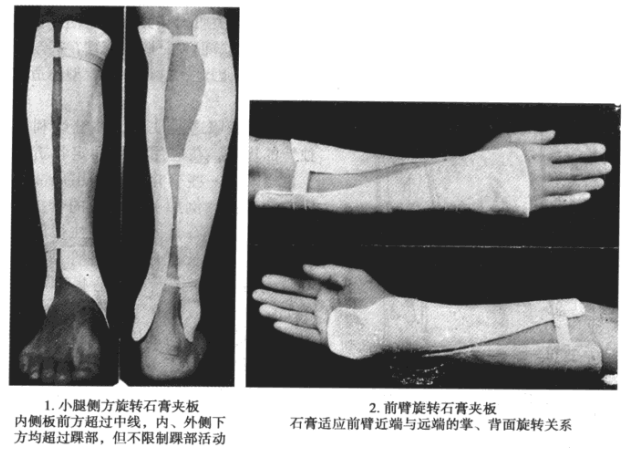

虽然石膏固定有上述若干优点,但也有较多不足之处。正由于石膏管型坚硬,与肢体贴合严密,所以难以适应肢体在创伤后的进行性肿胀,容易引起压迫而致血运障碍,甚至造成肢体坏死。而当肢体肿胀一旦消退,又会因石膏管型过松而致骨折再移位(图5)。在急诊复位固定后,如因位置不理想需重新复位固定时,拆除并更换石膏也是十分繁琐和困难的。

△ 图5 肢体消肿后,可因石膏管型过松而致骨折再移位